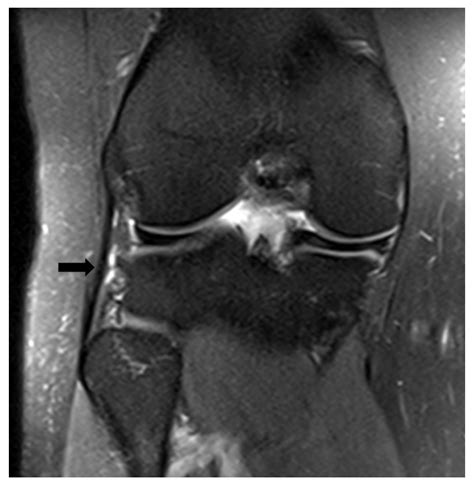

When you visit a physician, they will perform a physical examination to test the integrity of the Fibular Collateral Ligament. The most common test is the varus stress test. During this procedure, the examiner keeps the leg straight and applies pressure to the inside of the knee while holding the ankle. If the knee opens up more on the outer side than the uninjured knee, it indicates a tear.

Beyond physical exams, doctors may utilize imaging tools:

• MRI (Magnetic Resonance Imaging): The gold standard for visualizing soft tissues. It clearly shows the extent of a ligamentous tear.